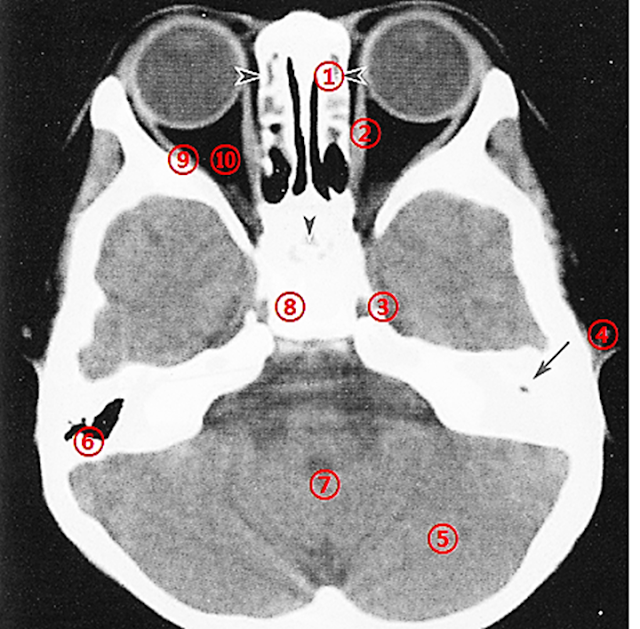

Axial CT Slice Through the Central Orbit

Normal Image

Image of a 4-Year-Old Male with Developmental Delay

Findings:

• Underdevelopment of the left mastoid air cells (Lt mastoid air cell) is observed, and the mastoid antrum shows soft tissue density rather than air.

• These findings are suspicious for chronic otitis media.

• The sphenoethmoidal sinus is undeveloped.

• A white appearance of the mastoid air cells on CT can be due either to poor development (chronic otitis media) or retention of fluid or secretions (acute otitis media).

• Bone window settings—achieved by increasing the window width and raising the window level—are useful for distinguishing between these two scenarios.

Advantages of CT Bone Settings:

Compared to traditional bone imaging techniques, CT bone window settings offer the following advantages:

1. Precision: CT provides detailed visualization of bony structures, enabling accurate planning and execution of realignment procedures.

2. Customization: Virtual reconstruction allows for treatment plans tailored to each patient’s unique anatomy and injury pattern.

3. Minimally Invasive: In some cases, CT-guided bone procedures allow for less invasive interventions, resulting in shorter recovery times and reduced risk of complications.